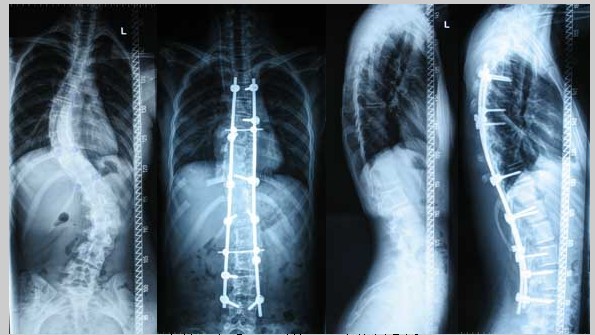

劳损性胸椎侧凸症